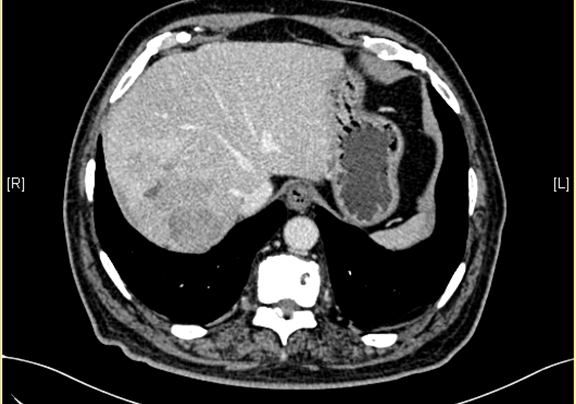

术前CT检查:

静脉期

下腹部增强CT示:肝右后叶上段占位,肝癌可能性大;右侧肾上腺占位,不除外转移瘤。